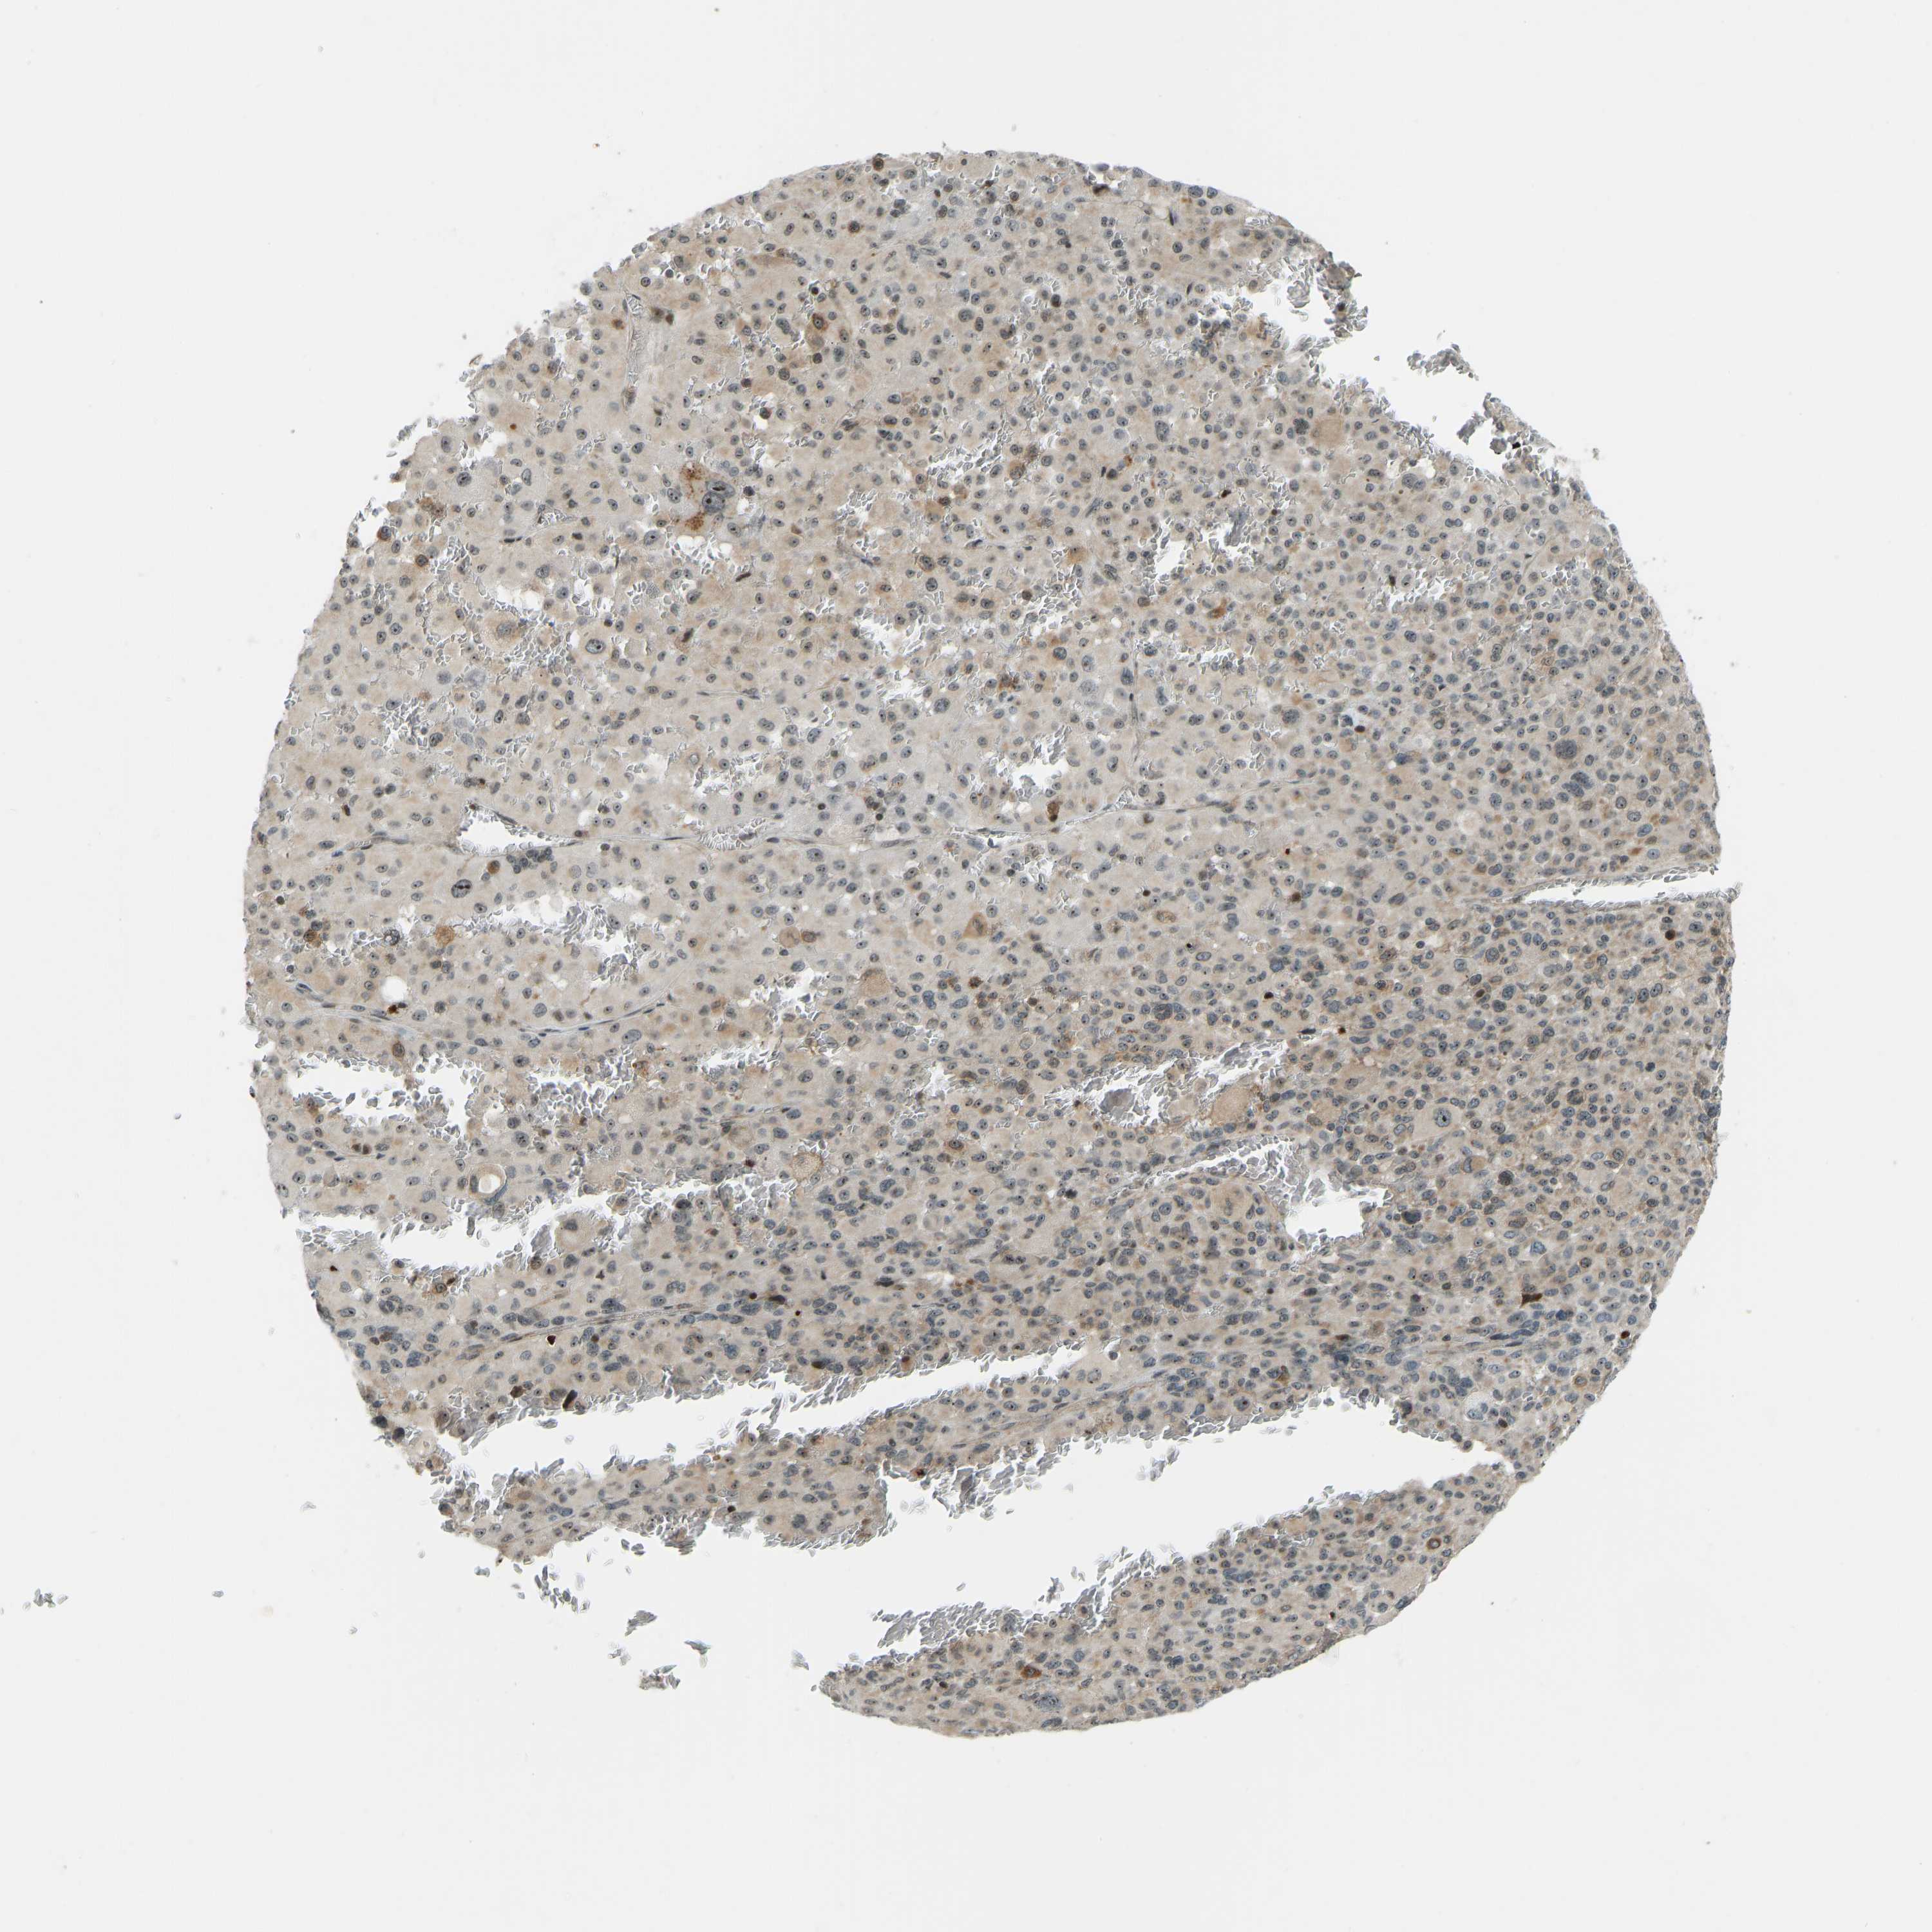

MELANOMA - Protein expressioni

A mouse-over function shows sample information and annotation data. Click on an image to view it in a full screen mode. Samples can be filtered based on level of antibody staining by selecting one or several of the following categories: high, medium, low and not detected. The assay and annotation is described here.

Note that samples used for immunohistochemistry by the Human Protein Atlas do not correspond to samples in the TCGA dataset.

Antibody stainingi

Antibody staining in the annotated cell types in the current human tissue is reported as not detected, low, medium, or high, based on conventional immunohistochemistry profiling in selected tissues. This score is based on the combination of the staining intensity and fraction of stained cells.

Each image is clickable and will lead to virtual microscopy that enables deeper exploration of all samples and also displays staining intensity scores, fraction scores and subcellular localization as well as patient and tissue information for each sample.

Antibody HPA018035

Staining

High

Medium

Low

Not detected

Intensity

Strong

Moderate

Weak

Negative

Quantity

>75%

75%-25%

<25%

None

Location

Nuclear

Cytoplasmic/membranous

Cytoplasmic/membranous,nuclear

Malignant melanoma, NOS

Malignant melanoma, Metastatic site